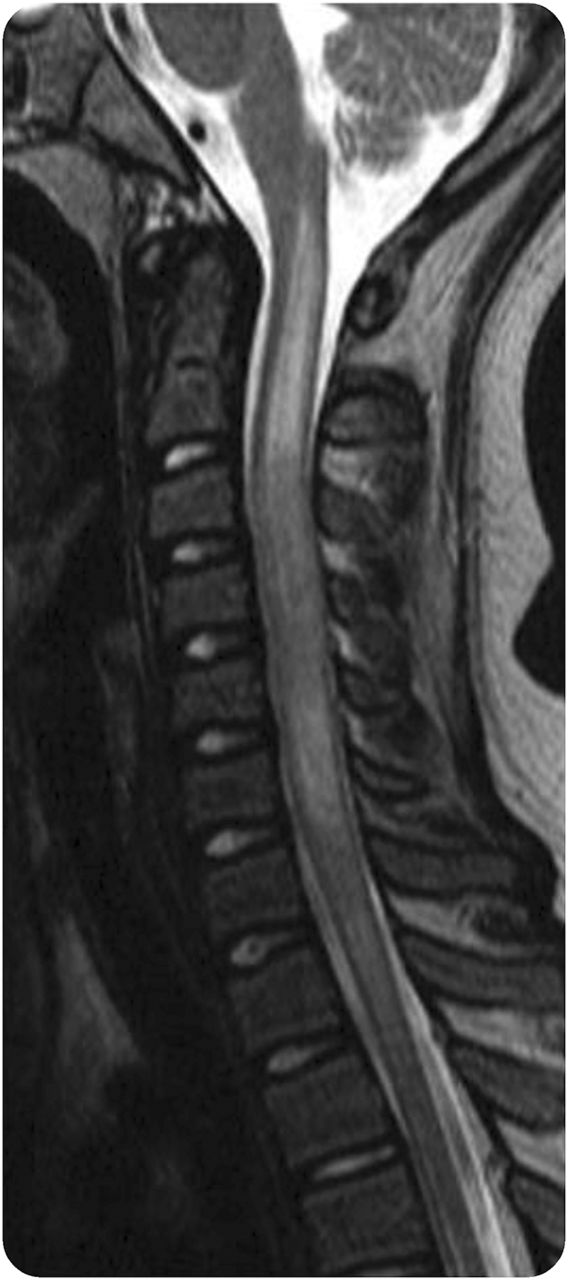

视神经的参与通常确认为高信号纵向视神经病变扩展/ > 1/2长度在t2加权或short-T1反转恢复图像,经常后方延伸到视交叉(图2)。急性通常被钆增强,同时可以看到视神经萎缩严重损坏视神经的慢性阶段。钆增强涉及眶脂肪组织可以观察到儿童在升高相关NMOSD (图3)。

虽然急性脊髓炎横没有观察到经常在演讲,它发生在大多数孩子在复发。4脊髓病变MRI上通常表现为广泛的集中位于高信号病变在t2加权像上跨越至少3段(图4)。脊髓出现肿胀,可能显示一个不规则的片状钆增强。颈纵向骨髓炎可能向上蔓延到脑干。非典型脊髓磁共振成像模式,但脊髓损伤最近一直在报道一个小女孩与血清反应阳性的NMOSD。21